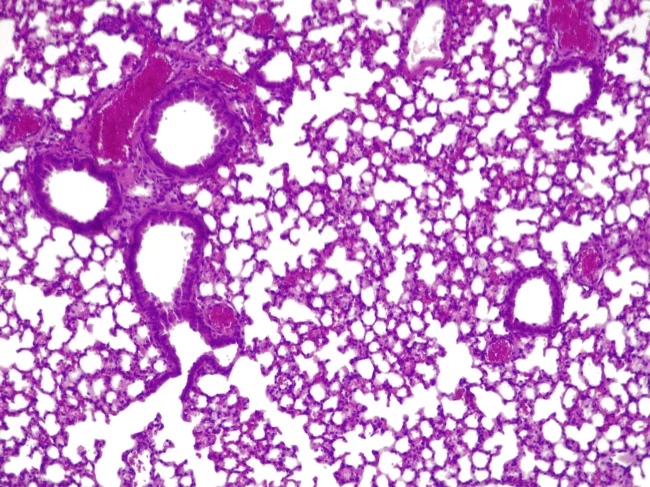

Cross-section of a mouse lung infected with P. aeruginosa and treated with engineered M. pneumoniae

Pulmobiotics is developing cell therapy for lung diseases, but with a twist

Pulmobiotics Ltd., which was founded in 2019, is developing cell therapy for lung diseases, including lung cancer. But unlike other cell therapies for cancer, this one is based not on harnessing T cells but on engineering bacteria. The team has engineered Mycoplasma pneumoniae to deliver various therapeutic proteins to the lung, depending on the therapeutic indication. Read More